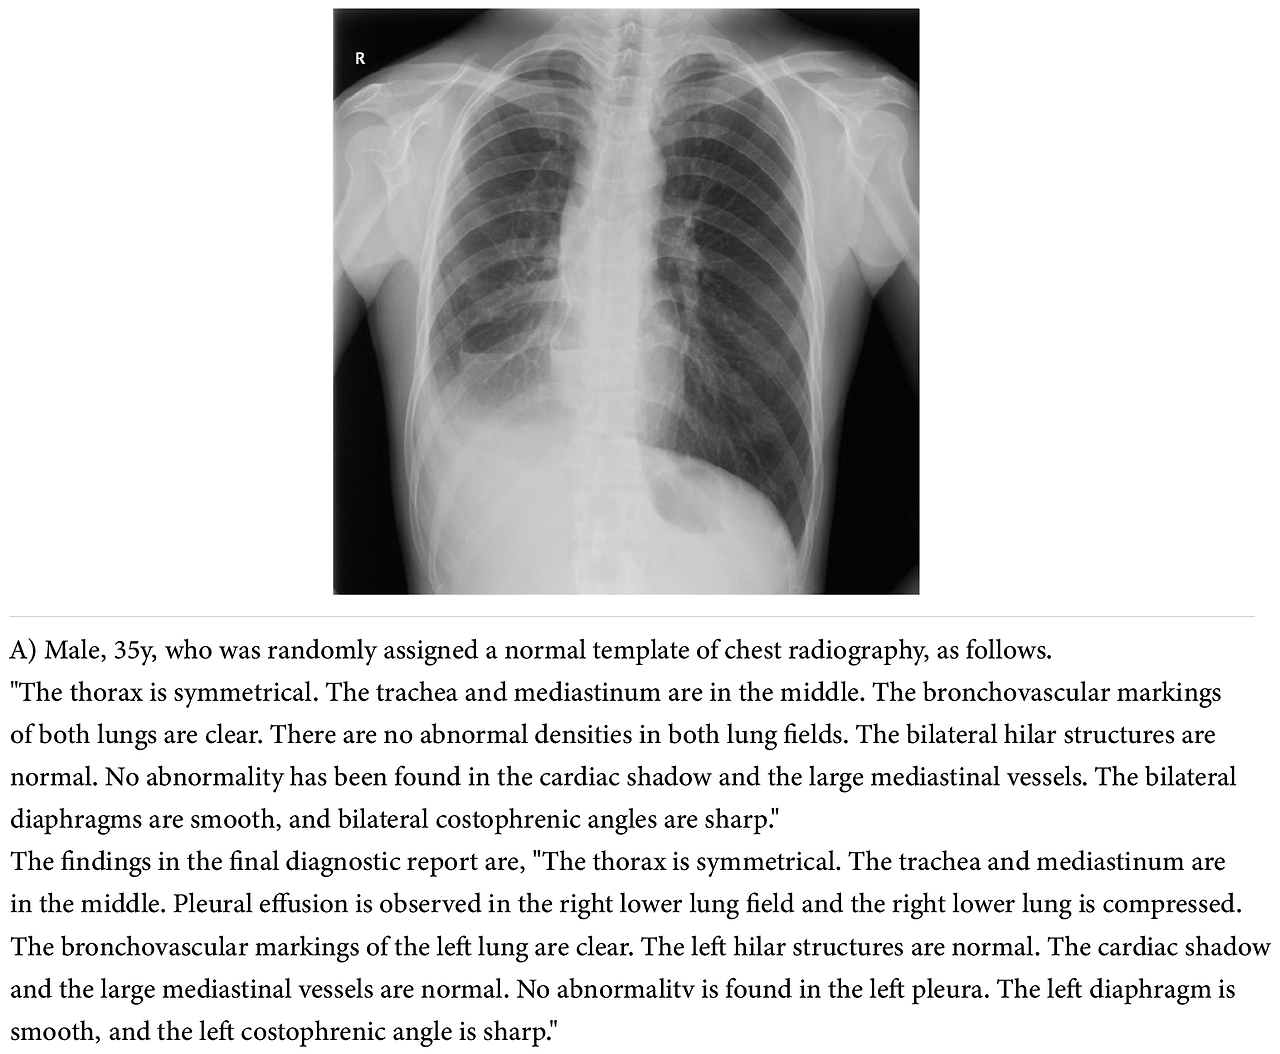

그림 2와 같이 전향적 테스트가 가능하려면 병원 전산 시스템의 도움이 필요하다는 것을 알 수 있습니다. 이런 전방위적 연구가 가능한 상하이 종합병원과 상하이 교통대학 의대 시스템이 부럽기도 합니다. 그리고 normal template의 예시를 보면 이렇게 자세한 판독문을 준다는 점이 놀랍기도 합니다. 그림 3은 supplement materials에서 보이는 eFigure 2의 한 예로 normal template 예시와 최종 판독문에 대한 것입니다. 사실 Normal template와 같은 판독문을, 한국에서 의사로 일하면서는 한 번도 보지 못했습니다. 본 논문을 리뷰하면서 국내 데이터로는 개발이 불가능하지 않을까 생각했지만, 카카오 브레인에서 초거대 AI로 X-ray 영상분석 서비스를 올해 상반기에 출시할 예정이고, 서울대병원에서 성능평가를 시작했다고 하니 기대해 봅시다. 구글 리서치에서 개발한 Med-PaLm2 모델도 USMLE 85점 수준이라고 하고, 최근 구글에서 Bard도 오픈했으니 우리는 이런 모델들의 성능을 어떻게 평가할까, 어떻게 잘 활용해 볼까를 고민할 시기입니다.

doctorsreview-03.png 그림 3 판독문 예시